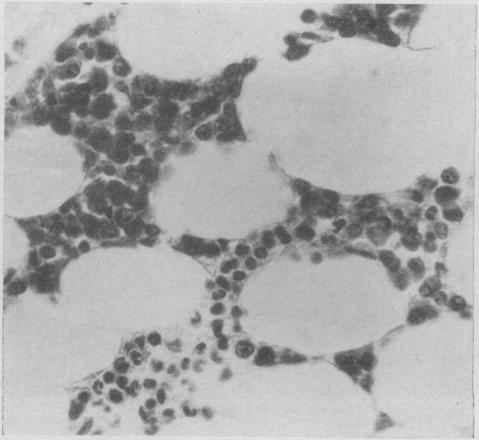

A method for the histological examination of bone marrow granules.

https://cdn.ncbi.nlm.nih.gov/pmc/blobs/6b53/1938706/2bfbefcd28e6/canmedaj00858-0037-a.jpg